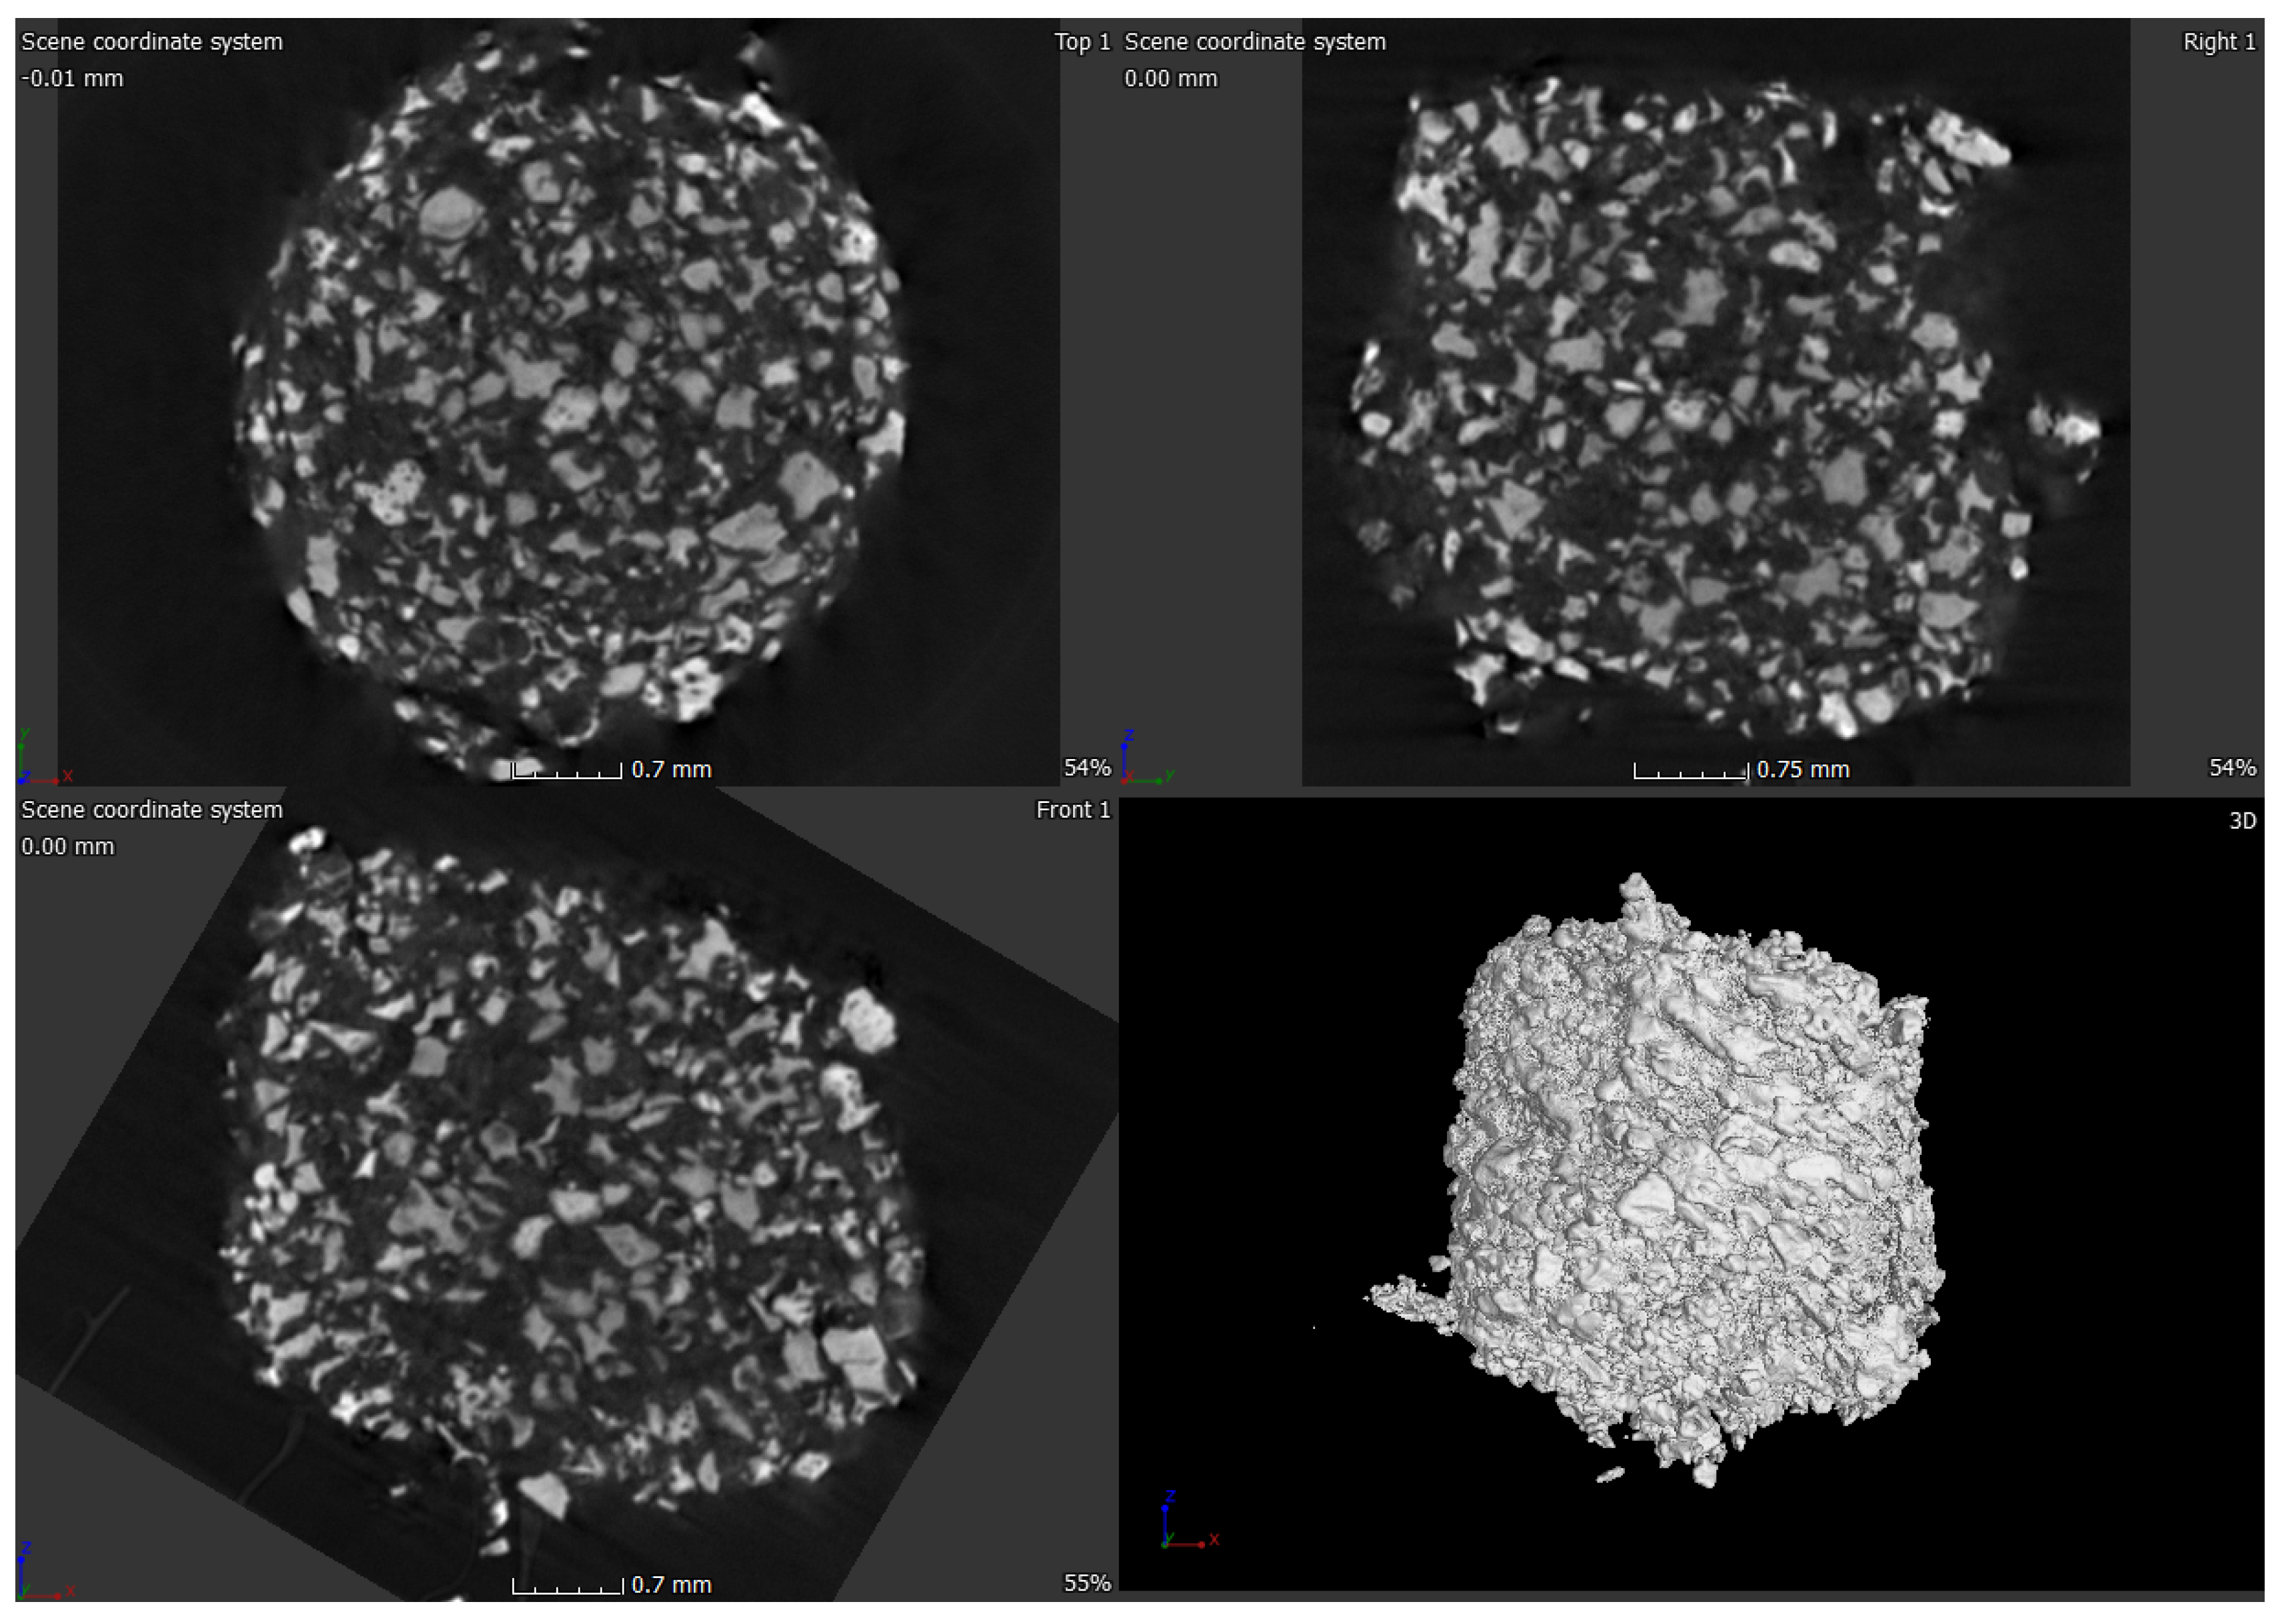

2.3. Micro-Computed Tomograpgy (μ-CT) of ABVF-BG Putty

μ-CT was done on the ABVF-BG putty to assess the distribution of BG particles in the polymer matrix of ABVF-BG. μ-CT of the ABVF-BG putty showed a homogenous distribution of BG particles embedded in the polymer matrix (Figure 7). The BG particles occupy 53.46% (v/v) volume in the ABVF-BG polymer matrix.

Figure 7.

μ-CT image of ABVF putty. BG particles appear to be homogenously distributed in the polymer matrix.

In addition to the traditional, albeit slightly slower, changes in the surface of the BG that leads to bone bonding and likely contribute to bone healing, the influence of porosity in this process cannot be neglected. In our current study, the sintered BG scaffold had a porous structure with varying pore sizes (Figure 3); this porosity was likely a result of the sacrificial polyurethane polymer template, although the variability of the pore sizes may reflect the partial structural collapse of the BG scaffold in the absence of the polymer template during the sintering process. Alternatively, variability in pore size may reflect incomplete penetration of BG slurry in the polyurethane template. Nevertheless, the range of pore sizes seen may prove important for vascularization and bone ingrowth. Different studies reported different pore sizes as optimal, but there is no clear consensus. Pore size ranges of 150–710 μm for bone tissue engineering [39], 5–600 μm for bone regeneration [40], 50 to 710 μm for bone regeneration, and 5 μm for neovascularization [41] have been reported. Although there is much variation in reports, it can be said that porous structure is necessary for bone tissue healing [42]. Although we did not use the sintered BG scaffold, nevertheless, the porous structure of the scaffold may be explored and utilized for other bone-tissue engineering purposes. In our study, we used crushed particles made from the sintered BG scaffolds (Figure 4a). Nonetheless, the ABVF-BG containing the particles showed a porous structure (Figure 6), which might have played a role in new bone formation in the in vivo study (Figure 11b). An SEM image of the crushed BG scaffold showed the particles used to formulate the ABVF-BG (Figure 4a). A zoomed-in view showed a densified structure of the particles with micropores, as noted in earlier studies [16]. Densification here is desired, as this would provide a measure of structural integrity under compression. The EDS of the sintered BG confirmed the presence of the elemental composition in the sintered BG (Figure 5) as was present in the amorphous 45S5 BG powder used. Additionally, ABVF-BG putty prepared with sintered BG particles showed a porous macrostructure throughout the composition (Figure 6b) as well as the presence of micropores throughout the structure (Figure 6c). Macroporosity likely resulted from the disbursement of sintered BG particles in a putty-like polymer matrix. The μ-CT of the ABVF-BG putty showed the homogenous distribution of the BG particles embedded in the polymer matrix (Figure 7). The packing density of the particles in the putty is a critical parameter that can be optimized to facilitate host bone cell infiltration and ingrowth. The BG-based ABVF-BG putty reported here has an appropriate spatial distribution of the BG particles in a degrading polymer matrix, which may be further optimized, offering a distinct advantage of our ABVF-BG putty over other BG particulate-only fillers [35]. Ultimately, the presence of both a macro and micro-pores as seen in the produced ABVF-BG putty would support bone tissue healing. In addition to that, the particle size distribution of the BG used in the AVBF-BG putty ranged from 175 to 425 μm; according to previous reports, bone graft substitute particle size ranges from 100 to 500 μm helped in more new bone formation compared to when smaller (<105 μm) or larger (1000–2000 μm) particle sizes were used [43,44,45].